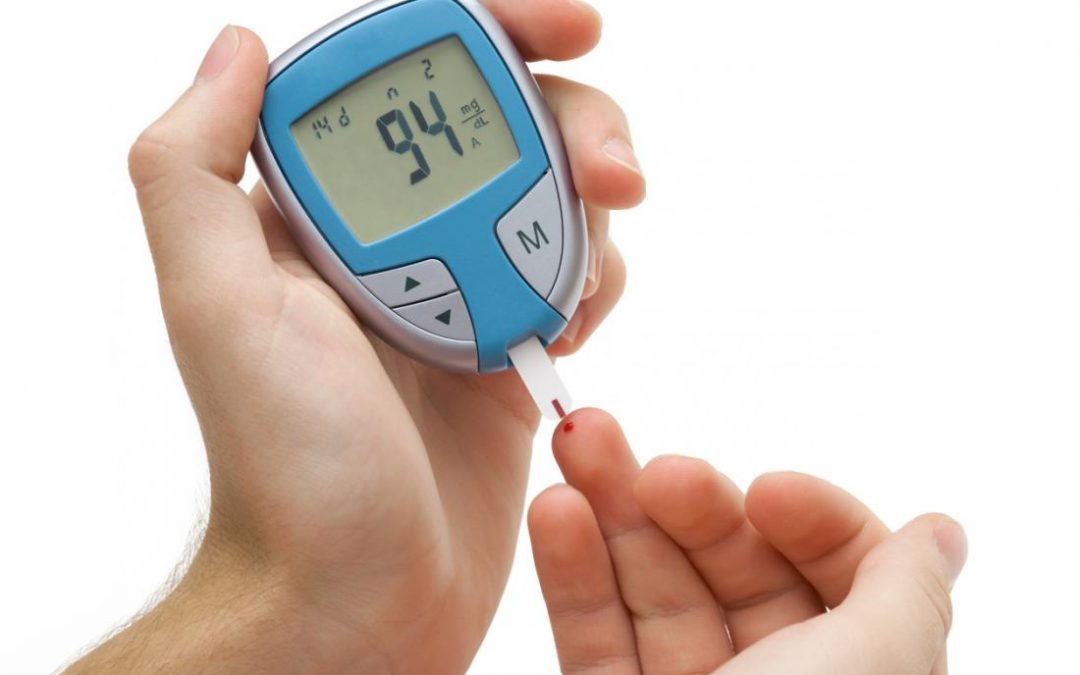

The Diabetes Checkup will offer diagnosis, testing, patient education, management help, and resources to fight diabetes. Your diabetes can be better managed when you are looking at the whole picture. Dr. Debabrata Sarkar<span...